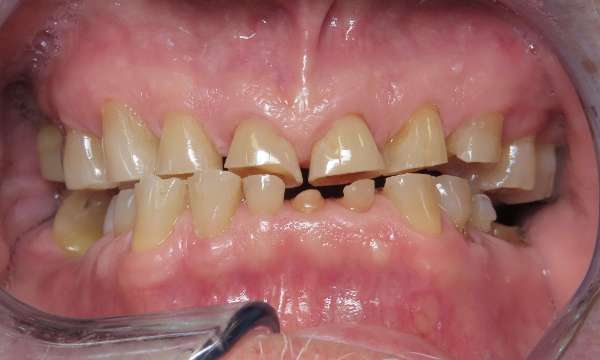

Full Mouth Restoration

This patient had severely worn most of his teeth from many years of clenching and destructive tooth grinding.  We were able to take him from his consultation, to a discussion of his options, to a final result of single crowns on most teeth with a bridge in the lower front.  We were so happy to deliver this result, improving his confidence, function, and quality of life.